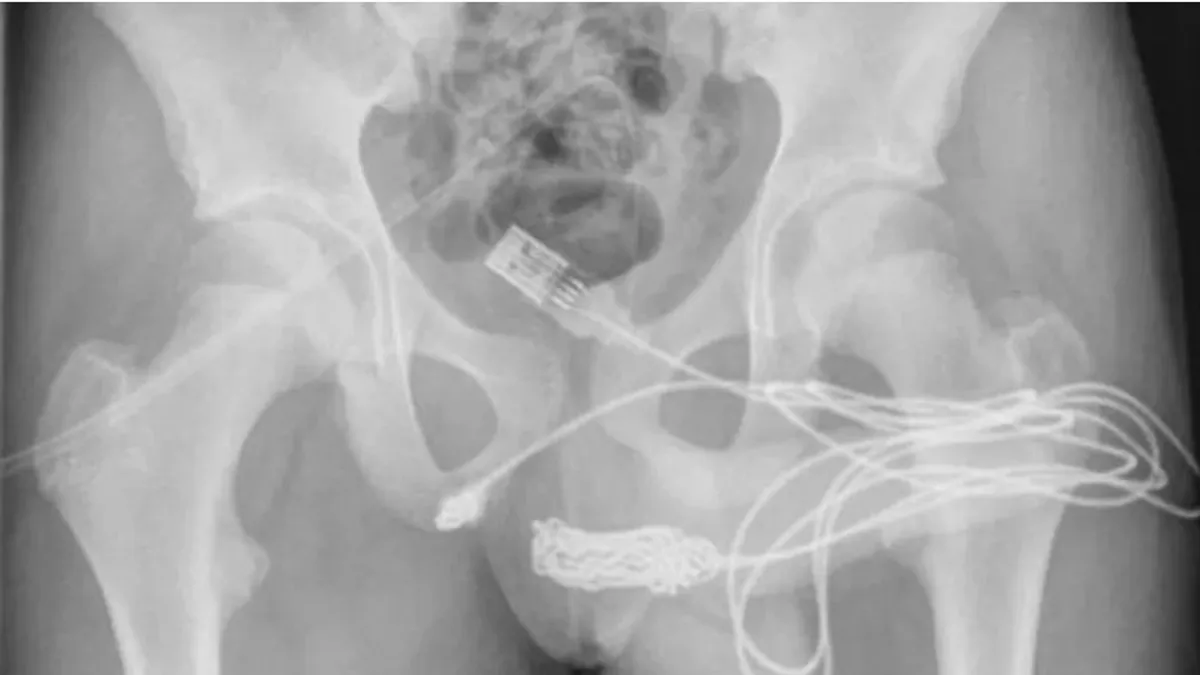

Para retirar o cabo o adolescente foi levado para a mesa de cirurgia. Uma radiografia mostrou que o cabo ficou preso na parte interna do pênis e embolado na uretra. Os médicos relataram o incidente e a extração do objeto em um relatório, divulgado no Science Direct.

“O paciente era um adolescente saudável e em boa forma, sem histórico de distúrbios de saúde mental. As duas pontas do fio USB estavam saindo do meato uretral externo, enquanto a parte do meio do fio permanecia dentro da uretra”, escreveram.